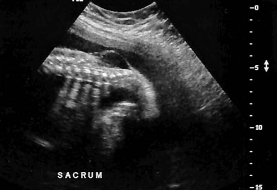

A sagittal image of the lower spine is most suspicious for:

spina bifida